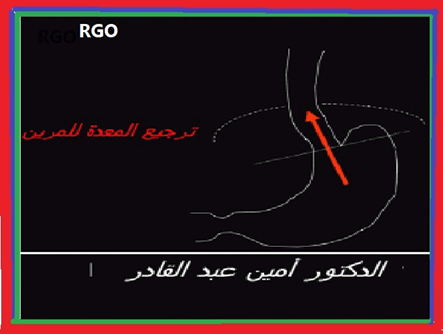

تتركز المؤشرات الرئيسية للعلاج بواسطة مثبطات مضخة البروتون (م م ب) على الارتجاع المعدي المريئي (ا م م ) (7)

. لقد بات الارتجاع المعدي المريئي مؤشرا عالي الجودة للعلاج بأدوية م م ت . والحقيقة فان الأعراض السريرية التي توحي بحالة أم م؟؟؟؟ تظل جد شائعة و في أكثر من مرة تبات سببا لتسليم وصفة م م ب أو ممارسة العلاج العشوائي بالنسبة لبعض الجزيئات م م ب (11). و غالبا ما تمسي تلك الأعراض مصدر تسليم وصفة العلاج العشوائي بالنسبة لبعض الأدوية م م ب التي تباع في الأسواق الحرة بدون تسليم الوصفة الطبية دون التأكيد المسبق دون التأكيد المسبق بتشخيص الارتجاع و لذلك فلا نستغرب بأن قرابة 40 % من ولائك الذين يتناولون عقاقير م م ب تصديا للأعراض التي توحي بحالة الجزر المعدي المريئي (ج م م ) باتوا غير راضين عن فائدة العلاج . وفي أكثر من مرة تعكس الاستكشافات التكميلية في هواته الحالات بأن المصابين لا تظهر عليهم علامات الإصابة بالارتجاع المعدي المريئي المرضي وتراهم يتناولون بالتالي العلاج الغير مناسب. لا يبدو أن هناك محلا لتوظيف أحسن الأدوية م م ب كلما برز شك في الاصابة بحالة ا م م (12) لوضع حد لاستسلام الغير مفيد للوصفات الطبية وتفاديا لحالات الإخفاق.

تحتل أدوية م م ب المحل الرئيسي في أخذ موقف علاج حالة الارتجاع المعدي المريئي. يبات ا م م أقل حموضة وبالتالي أقل تسمما للغشاء المخاطي المريني (13) الأمر الذي يؤول الى سرعة التئام الآفات أو جروح الالتهابات المريئية (14). بجانب تحقيق وتراجع الأعراض الناجمة عن الارتجاع المعدي المريئي يتم اللجوء الى تناول م م ب . بجانب تحقيق وتراجع اعراض الناجمة عن الارتجاعي المعدي المريئي. يتم اللجوء لتناول م م ب قصد التئام التهاب المريء الناجم عن حالة الترجيع المعدي المريئي للوقاية ضد الانتكاسات التي تبرز بعد التئام الجراح بجانب علاج حالة الجزر المعدي المريئي الذي تخلفه عقاقير ا م م البروتون التميز بالأعراض السريرية و وجود الدم في البراز. تختلف الجرعات الموصي بها حسب وجود أو عدم التهاب المريء. يلخص جدول رقم 1